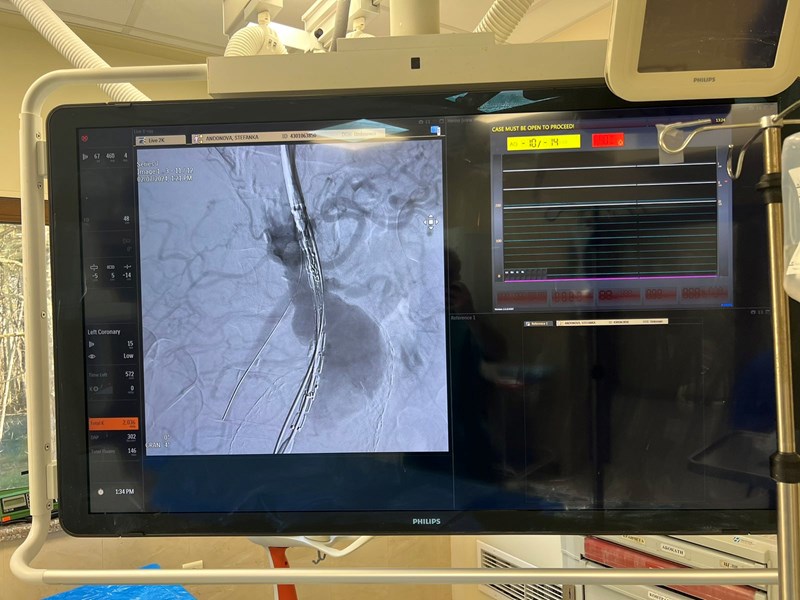

Уникалното в тази интервенция е, че е изработена протеза с четири фенестрации (отвора). Следващата стъпка е поставяне на специални стентове в четирите висцерални артерии ( двете бъбречни артерии, целиачната артерия и мезентериалната артерия). Едновременно с това се извършва изключване на двете илиачни аневризми. Съчетанието на абдоминална и илиачна аневризма се наблюдава в 30% от случаите. Тази патологична комбинация изисква значителни теоретични и хирургични умения.

В конкретния случай операцията продължи близо 10 часа. Чрез малки разрези в областта на бедрените артерии, под рентгенов контрол в хибридна операционна зала, д-р Асен Тодоров и неговият екип спасиха живота на възрастната жена и ѝ дадоха шанс да живее нормално.